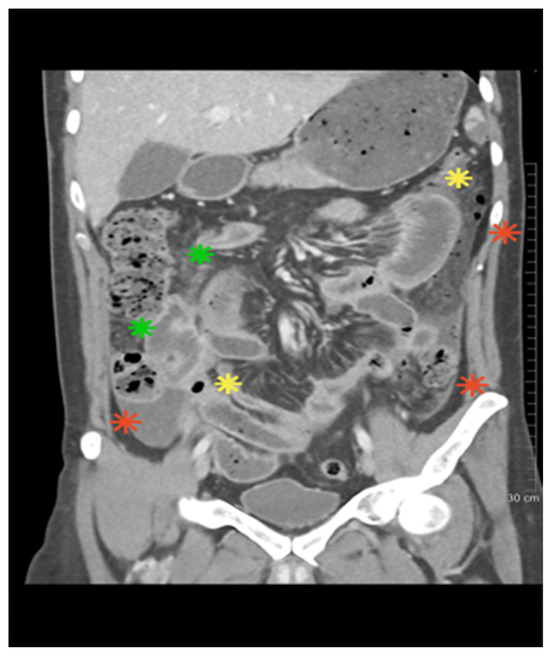

Hydatid Cyst in Pregnancy—A Diagnostic and Therapeutic Dilemma: Study Case Report

by Liliana Steriu, Ionut Eduard Iordache, Antonia Bisinicu, Bianca Andreea Steriu, Gabriela Baltatescu, Andreea Nelson Twakor, Eugen Dumitru and Vlad Tica

J. Clin. Med. 2025, 14(14), 5073; https://doi.org/10.3390/jcm14145073 - 17 Jul 2025

Cited by 2 | Viewed by 1893

Abstract

Background: Hydatid disease, caused by the larval form of Echinococcus granulosus, is a rare but potentially life-threatening condition during pregnancy, with an estimated incidence of 1 in 20,000 to 30,000 gestations. Physiological immunosuppression and increased placental steroid levels during pregnancy may promote cyst [...] Read more.

Background: Hydatid disease, caused by the larval form of Echinococcus granulosus, is a rare but potentially life-threatening condition during pregnancy, with an estimated incidence of 1 in 20,000 to 30,000 gestations. Physiological immunosuppression and increased placental steroid levels during pregnancy may promote cyst growth, elevating the risk of rupture, which can result in anaphylactic shock, sepsis, or widespread peritoneal dissemination. Diagnostic imaging, particularly ultrasonography, plays a central role in detection, while treatment decisions are complicated by the lack of standardized guidelines and the need to balance maternal–fetal safety. Methods: This case report describes a 29-year-old pregnant woman at 22 weeks’ gestation who was incidentally diagnosed with two large hepatic hydatid cysts during a routine ultrasound. Results: Given the high rupture risk, she underwent successful laparoscopic surgery in the second trimester, followed by careful monitoring and elective cesarean delivery at term. A third retroperitoneal cyst, initially managed conservatively, was excised postpartum. Conclusions: This case highlights the critical importance of individualized, multidisciplinary management in achieving favorable maternal and neonatal outcomes in complex presentations of hydatid disease during pregnancy. Full article

(This article belongs to the Section Obstetrics & Gynecology)

Show Figures

Figure 1